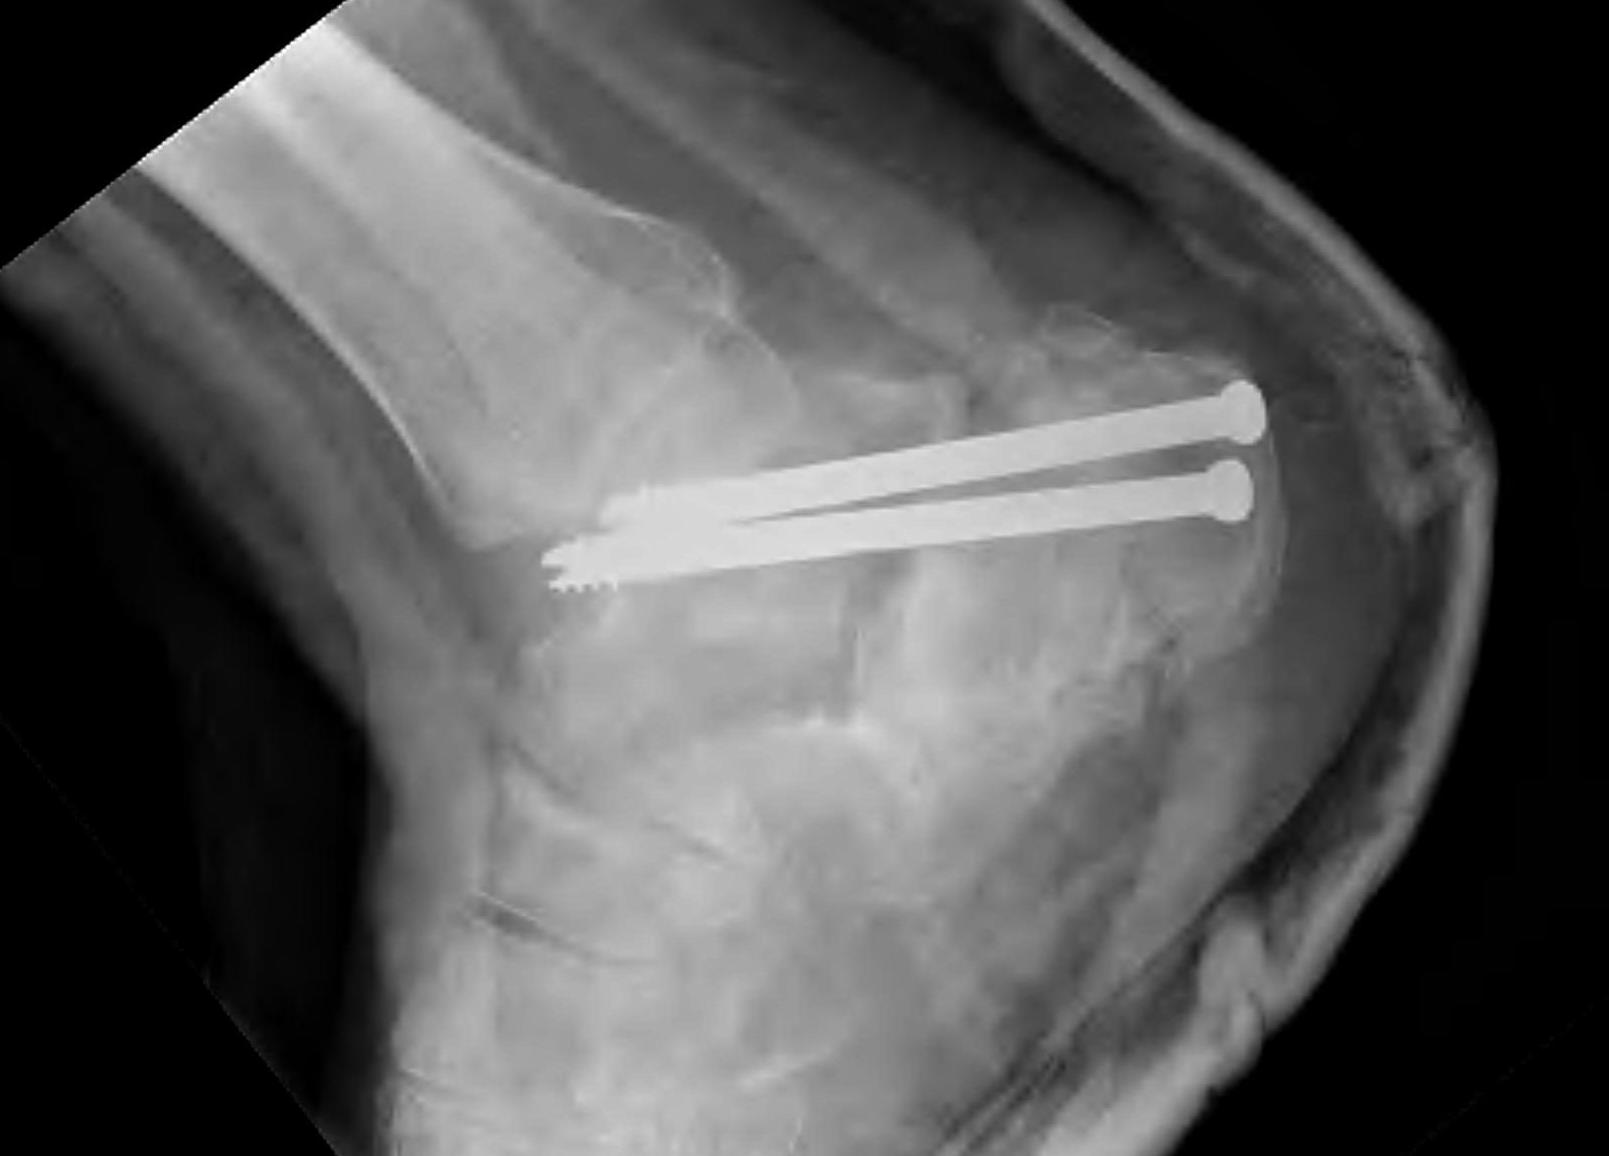

- 287 displaced intra-articular fractures

- MUA / Gissane spike percutanous reduction / K wire fixation

- 72% good or excellent results

- 1.7% deep infection, 7% superficial infection